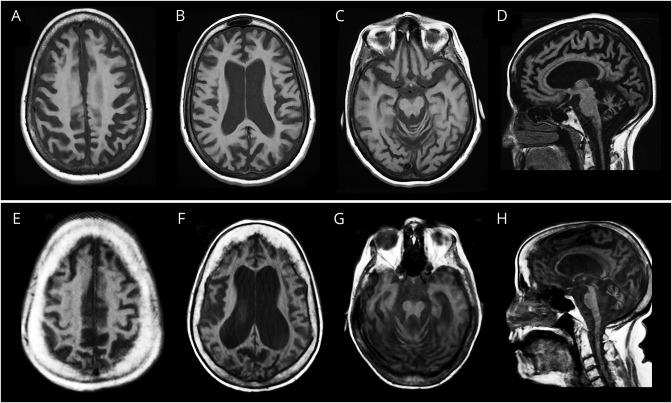

We report the clinical, imaging, molecular, and nucleotide excision repair (NER) capacity of 2 middle-aged women with progressive neurodegeneration ultimately diagnosed with XP-F.

Both patients presented with adult-onset progressive neurologic deterioration involving chorea, ataxia, hearing loss, cognitive deficits, profound brain atrophy, and a history of skin photosensitivity, skin freckling, and/or skin neoplasms. We identified compound heterozygous pathogenic mutations in and confirmed deficient NER capacity in skin fibroblasts from both patients.